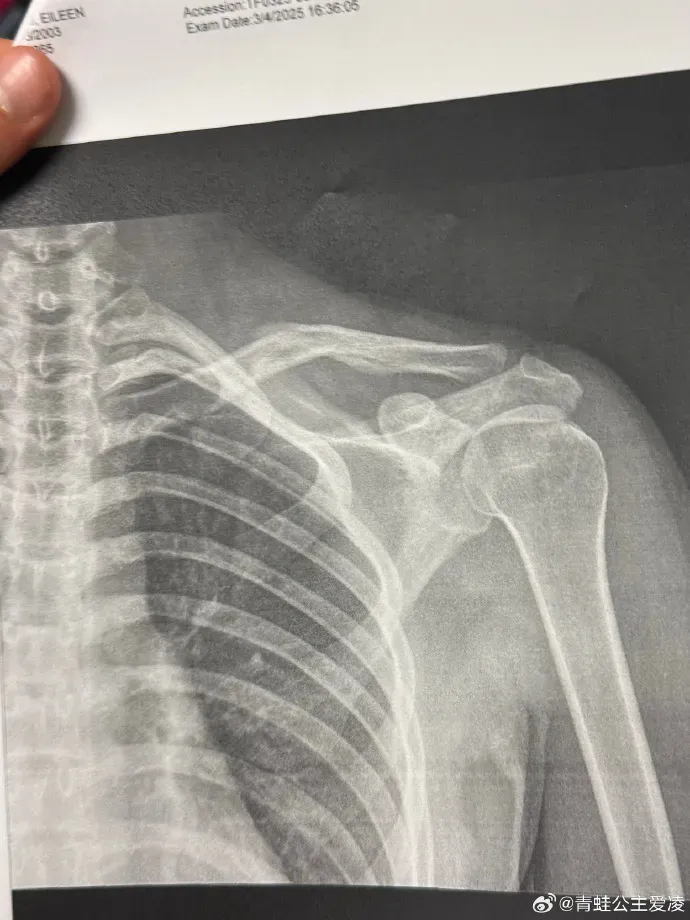

本年3月9日,谷爱凌在外交媒体晒出肩部骨折的X光像片,并配上一个心碎的颜料,随后关系话题登上热搜。